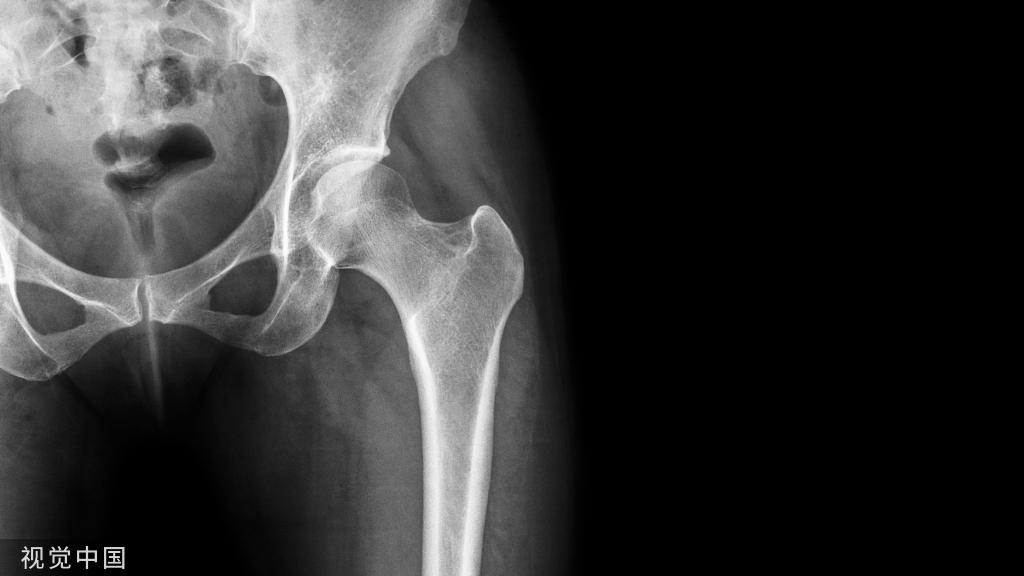

01正位片

观察有无寰枢关节脱臼,齿状突骨折或缺失(张口位片);第七颈椎横突有无过长,有无颈肋。钩椎关节及椎间隙有无增宽和狭窄。